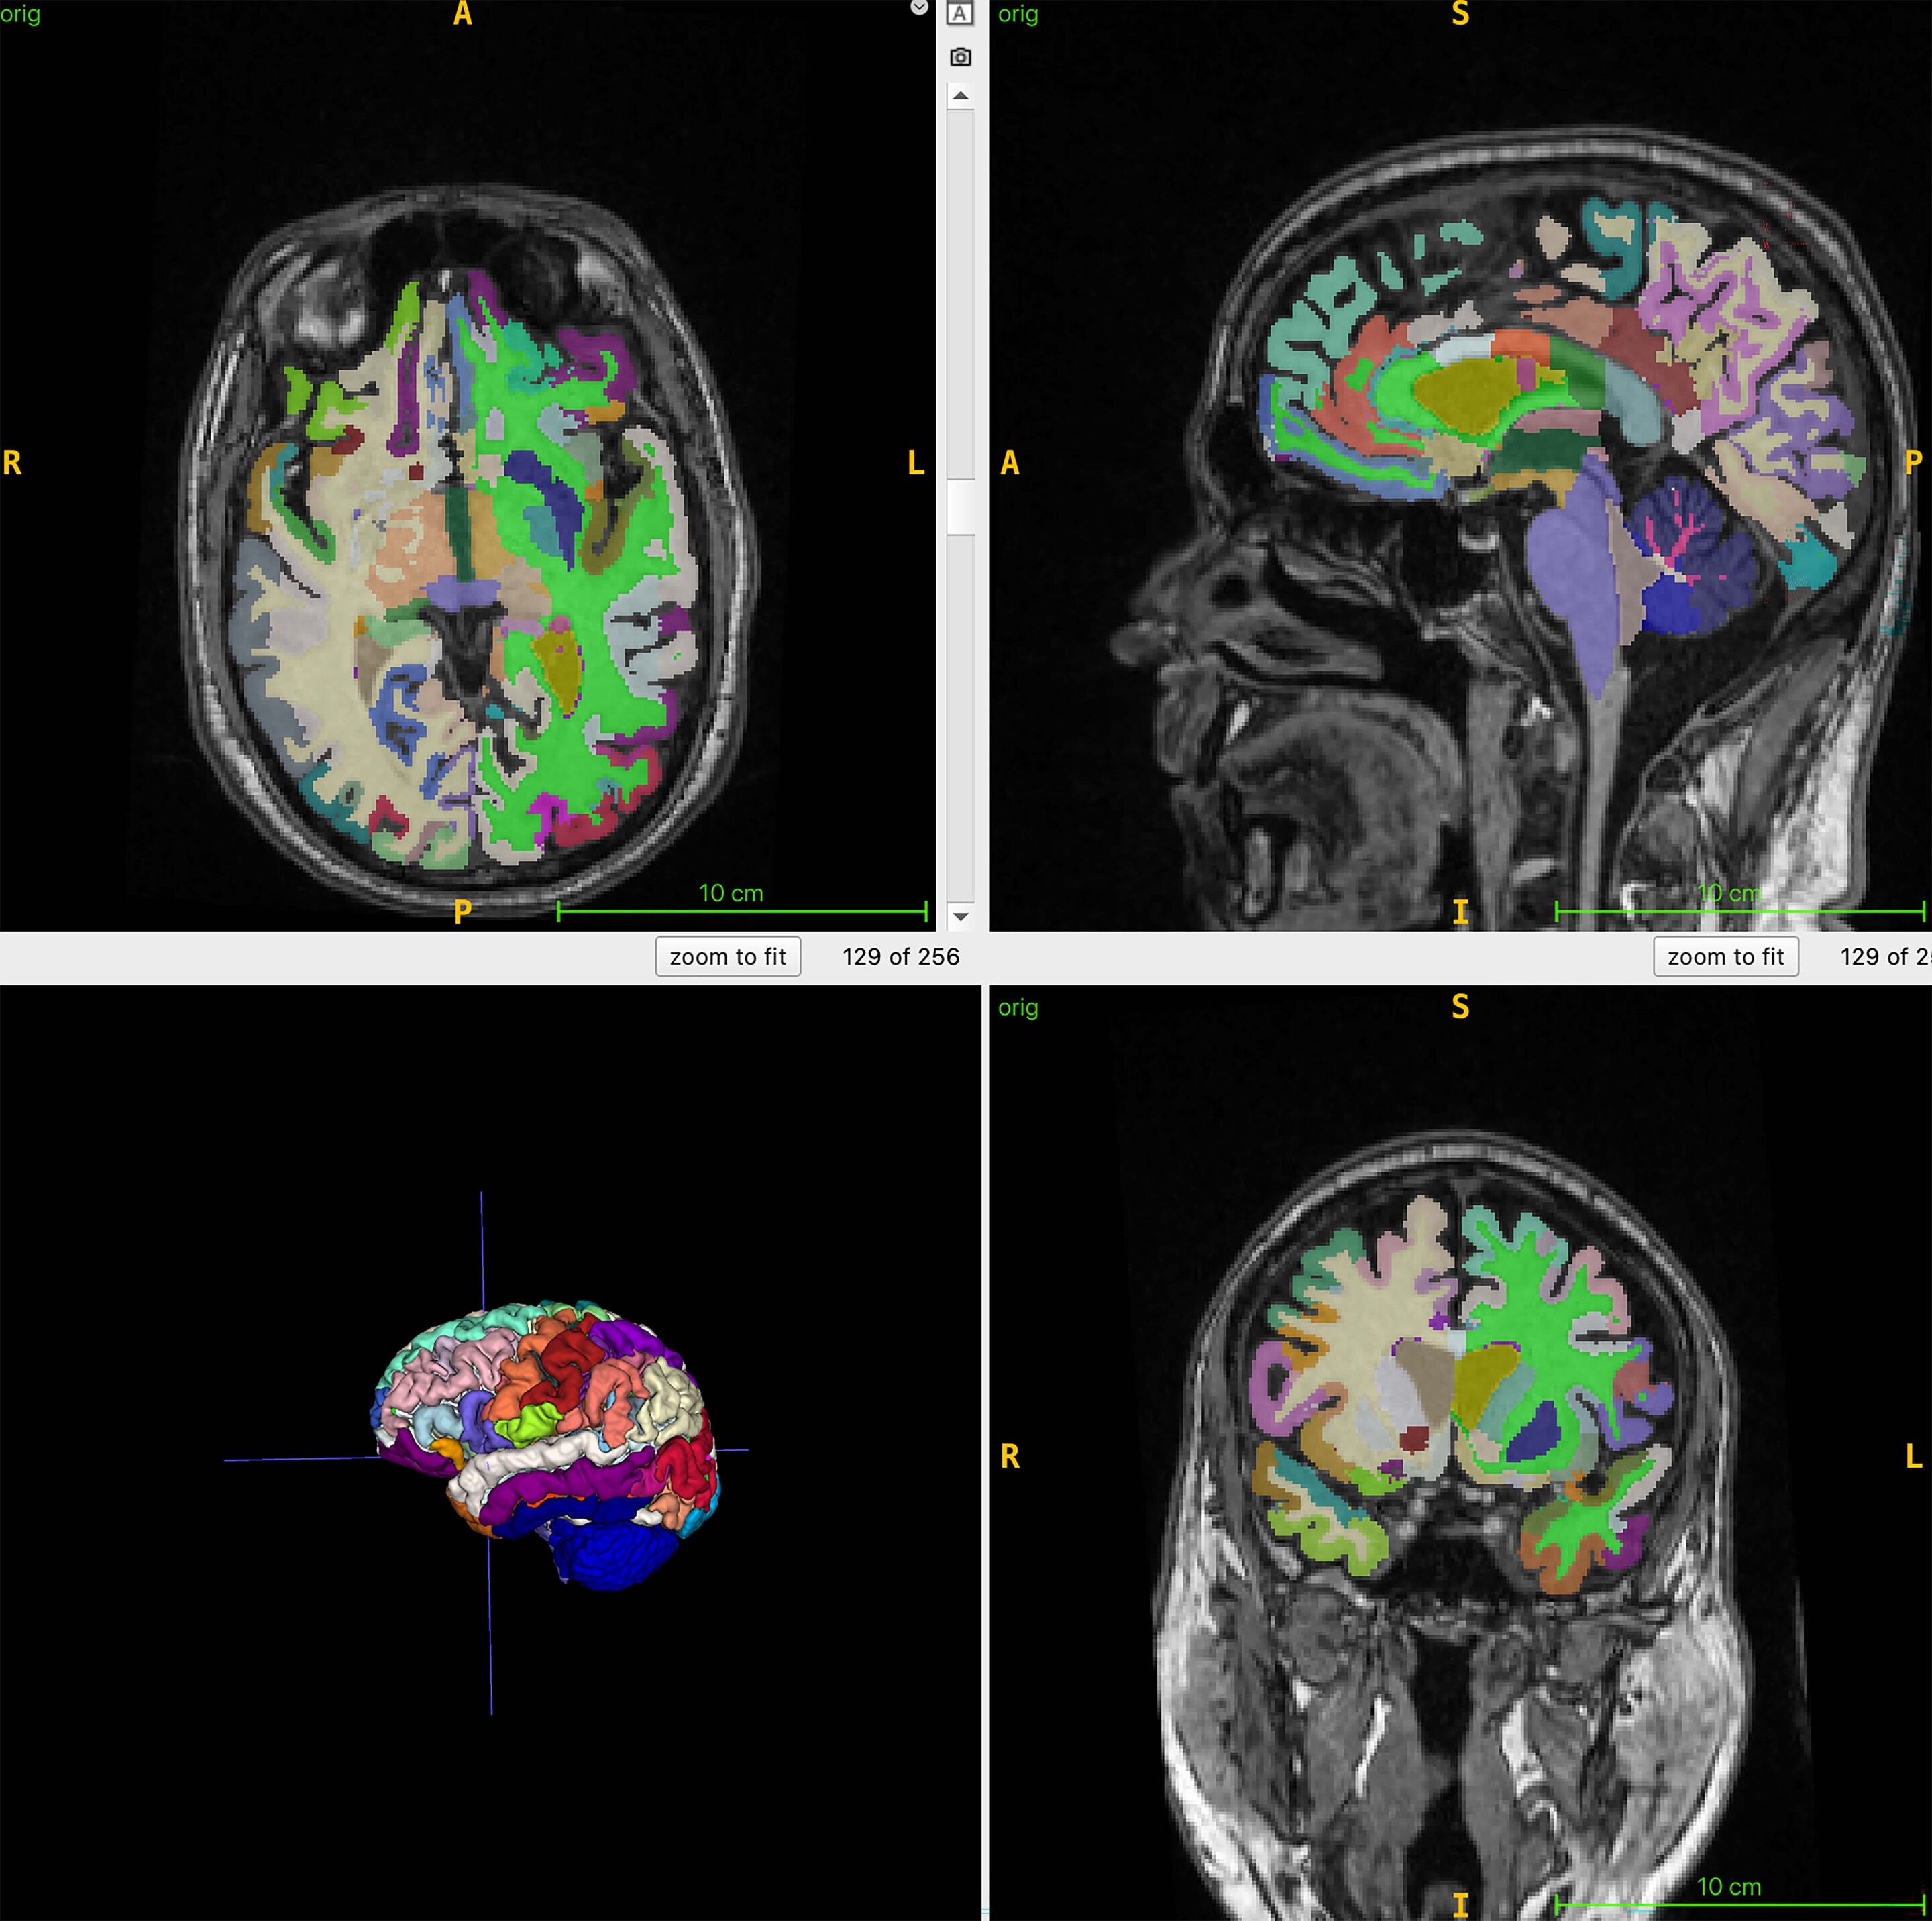

Brain age is the computational estimate of chronological age from structural MRI of the brain. Muscle mass, monitored by body MRI, can be an indirect marker for many interventions aimed at reducing frailty and improving brain health, and brain lifespan predicted by structural brain imaging can provide information about risk factors for Alzheimer’s disease, such as muscle loss.

The average chronological age of the participants was 55.17 years. The researchers combined MRI images with T1-weighted sequences, a technique that produces images in which fat appears bright and fluid appears dark. This allows optimal imaging of muscle, adipose and brain tissue.

An artificial intelligence (AI) algorithm was used to measure normal total muscle volume, visceral fat (hidden abdominal fat), subcutaneous fat (fat under the skin), and brain age.